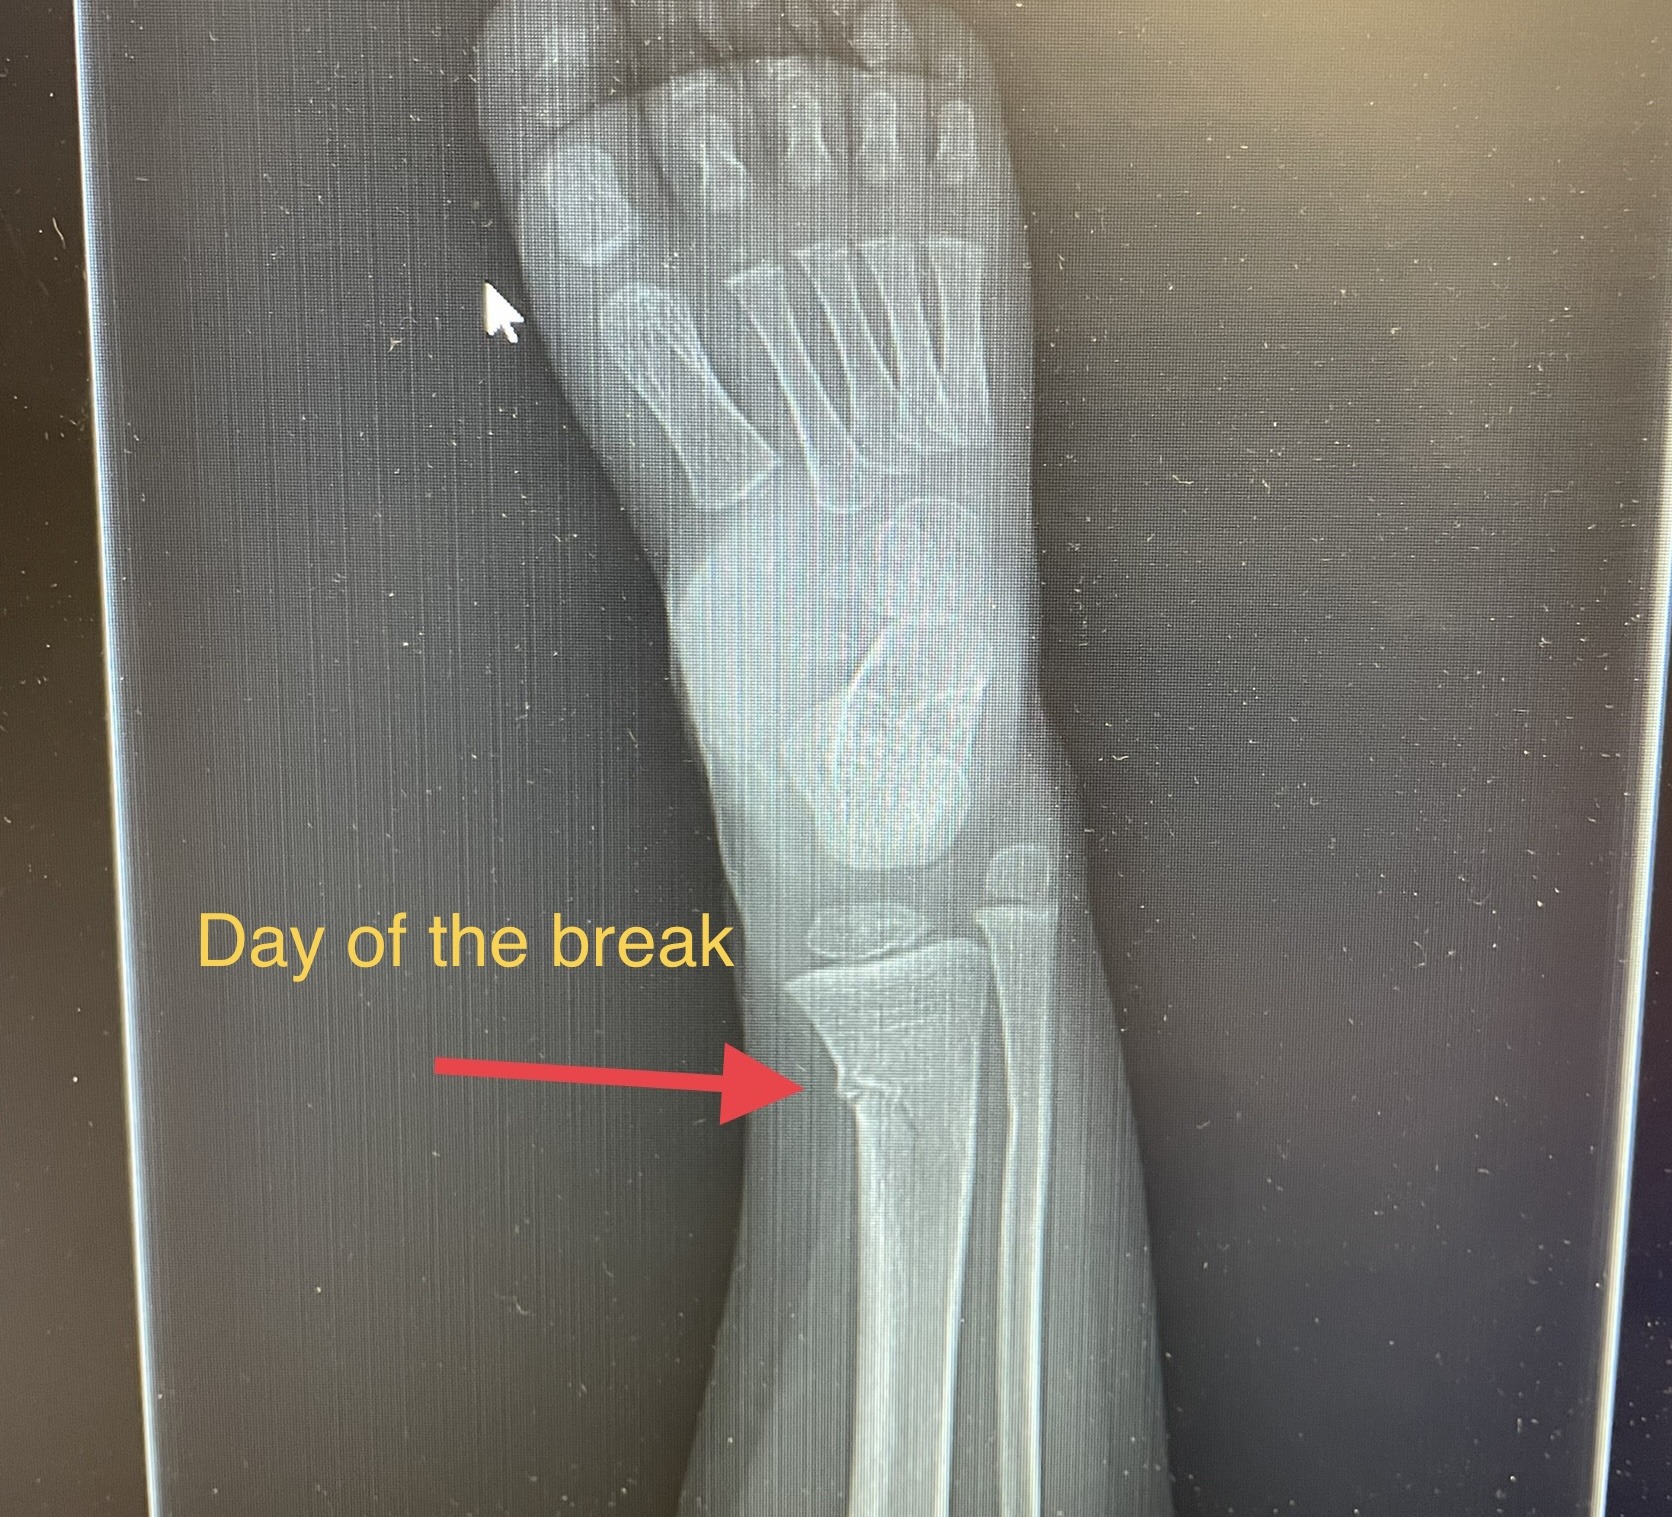

Last month my 2 year old daughter slid awkwardly down a playground rock wall and broke her leg. Specifically, she had a mild tib-fib fracture. That stands for tibia and fibula which are the two bones of the lower leg. That first week was terrible. We had a child with 2 year old opinions stuck with the mobility of a 7 month old. By the third week of having the cast, she was running and jumping in the cast. After just three weeks they removed the cast! Three weeks! When kids are that young their body heals extremely fast. I would not wish that experience on any kid or parent but… as a medical professional, I found it fascinating! Now I get to share a little about the bone healing process with you using her actual x-rays.

After the initial break your body mounts that inflammatory response. This is an important step for removal of any waste or foreign bacteria but also to bring nutrient rich blood to the area. After the inflammatory phase your body creates a callous around the bone. This callus is initially soft but as those osteoblasts work that callus hardens and the break is surrounded by more bone than it needs. That area is now strong but it is not the ideal shape for function and energy transfer and so your body begins to remodel and slowly shave down the bone back to the perfect shape. Incredible!